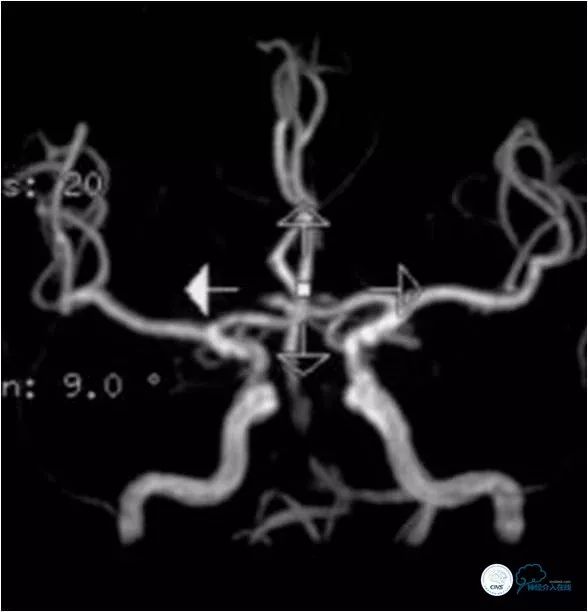

MRA示基底动脉近段重度狭窄(图2)。

图2